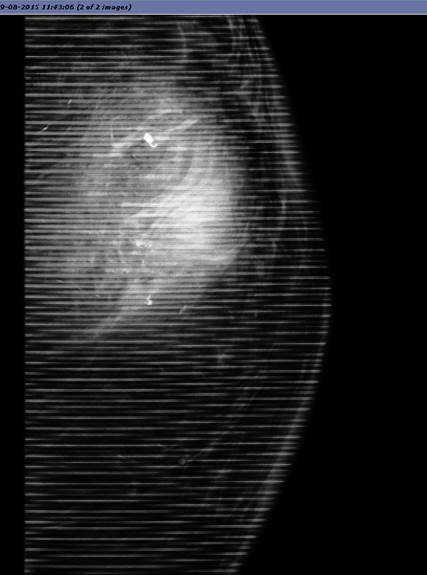

GE_grid_artefact.jpg